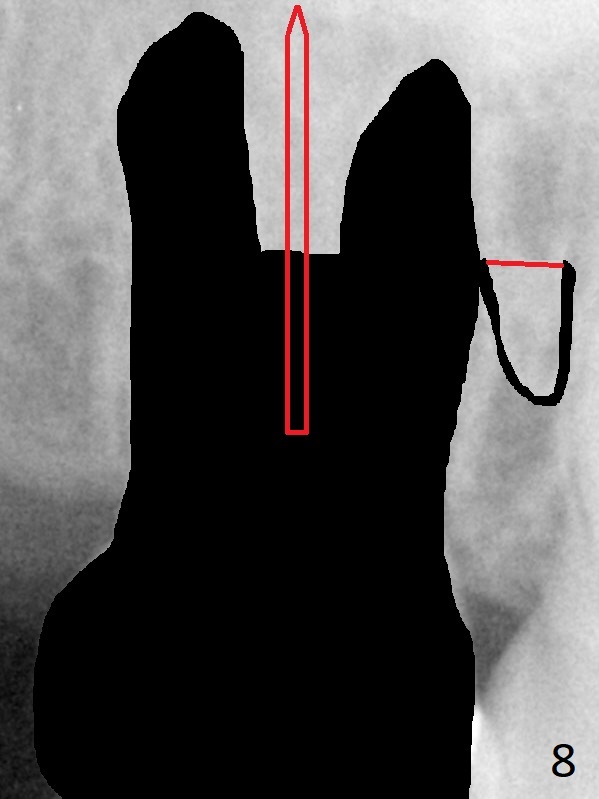

A 58-year-old woman has had RCT done at #2 for several years. The roots are trifurcated with sufficient bone height (Fig.1-3). Recently the tooth becomes symptomatic with formation of a distal fistula (Fig.4). After extraction, the septum (Fig.5 S) may be wide enough for initial drill (Fig.6). If not, resection the thin part of the septum (Fig.7 red line, with small or medium Rongeur) and use the initial drill (Fig.8). Anyway, take PA immediately to avoid sinus membrane perforation. If possible, adopt single drill technique.